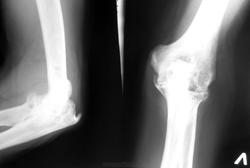

Случай №2 Мужчина 60 лет. Уже 8 лет беспокоят боли в голеностопном и локтевых суставах. Ранее нигде серьёзно не обследовался. Ставили РА. Я написал в заключении ДОА и диф. ряд с сирингомиелией.

По локтевым - изменения вероятно обусловлены артритом - остеопороз, кистовидные просветления или очаги деструкции?  (справа  сильнее - вроде как узурация) + выраженный вторичный артроз с 2-х сторон. Какой артрит - надо разбираться (клиника, лаб. данные), если ещё и голеностоп - более вероятен системный характер поражения.